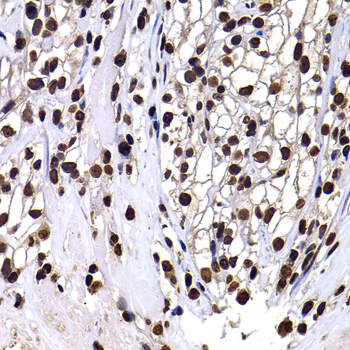

Immunohistochemistry of paraffin-embedded rat spleen using Histone H3 antibody.

Immunohistochemistry of paraffin-embedded human kidney cancer using Histone H3 antibody.

Immunohistochemistry of paraffin-embedded mouse cancer using Histone H3 antibody.